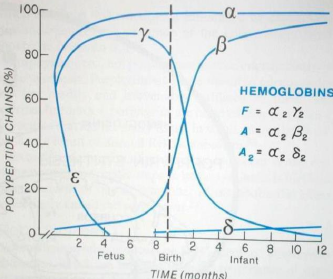

Thalassemia 地中海/海洋性貧血

- α-Thalassemia

- α 出問題, 只有 4β 或 2β2δ

- 嚴重,易死胎

- β-Thalassemia

- β0: 較常見,完全無 β

- β+: 較少見, β 少